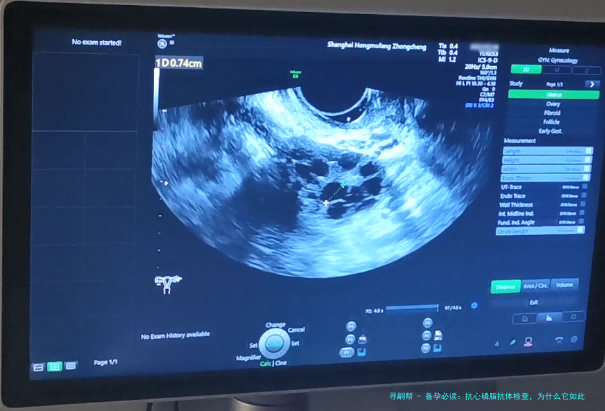

什么是抗心磷脂抗体?它为什么和备孕扯上关系?

为什么备孕要查抗心磷脂抗体?背后的原因大揭秘